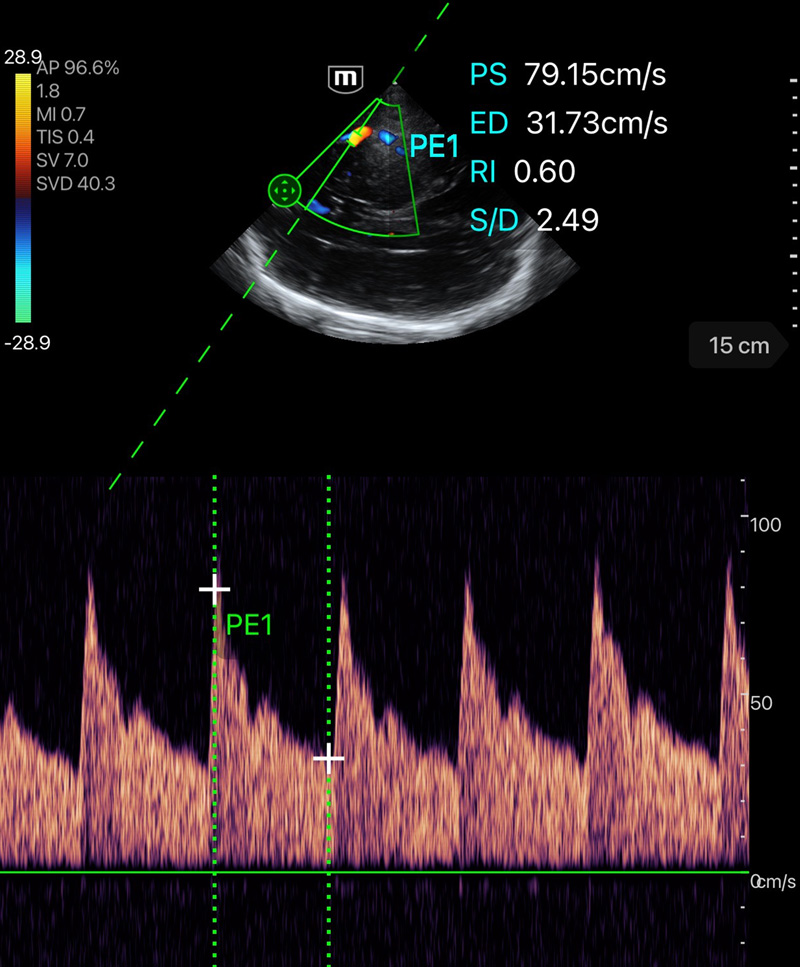

Clinical Images

Mitral and Tricuspid Regurgitation

Clinical Images

Mitral and Tricuspid Regurgitation